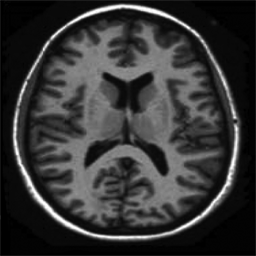

In Figure 1.1 the influence of the choice of a constant in (1.1) is shown, over-regularising the reconstructed image if chosen too small and under-regularising if chosen too large. Moreover, in Figure 1.2 the reconstructed images with constant and spatially-dependent are shown, where has been optimized with the bilevel approach for (1.1) proposed in [9].

4.1. Uniform Gaussian noise

In this first experiment, we consider the denoising problem with brain scan images. The first set consists of images of pixels and Gaussian noise with zero mean and variance . The original and noisy images are shown in Figure 4.1. The domain decomposition-semismooth Newton algorithms run with the parameter values , , and . The results are shown in Figure 4.2. From the surface representation of , we can observe that is continuous and its shape is related to the one of the original image. In particular, the regularization is stronger in homogeneous regions in the image, and weaker where the image intensity undergoes variations on a smaller scale.